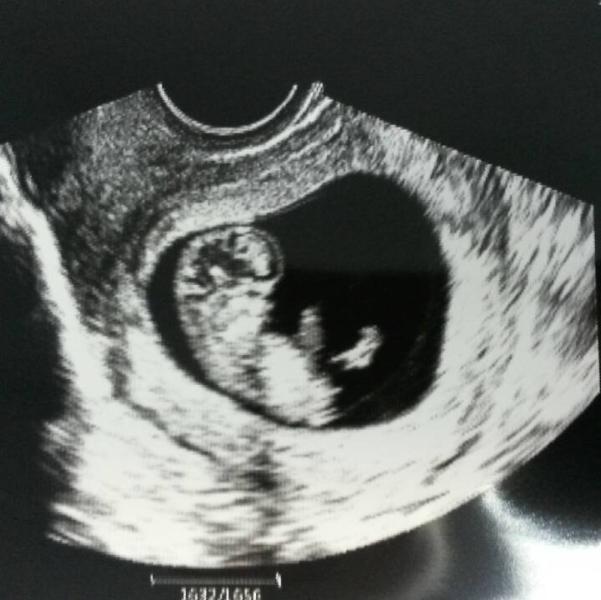

Я ревела!!!Это чудо!!!Дергает и ручками и ножками))) По сердцебиению на 70% девочка😂

и я вчера делала узи, тоже 9,5 недель у меня. такое умиление) подскажите, пожалуйста, какое сердцебиение у вашего малыша? а то мне ничего про предположение пола не сказали